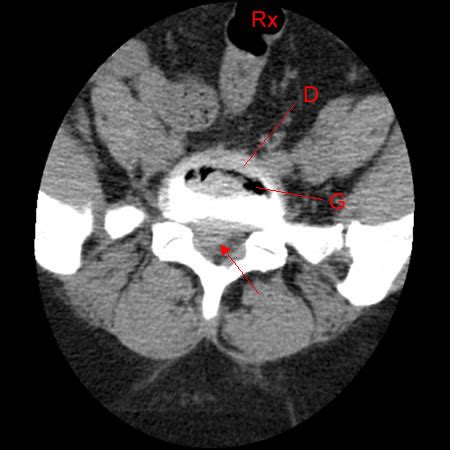

Webvue arrière d'un homme souffrant d'une douleur dorsale lombaire aigue ou d'une hernie discale ou d'un lumbago avec l'imagerie de rayon x d'épine dorsale à. WebLa radiographie du rachis lombaire peut être normale ou mettre en évidence des signes de discopathie sous la forme d’une perte de la hauteur discale normale. L’IRM et le scanner. WebLa hernie discale, située entre les vertèbres L4 et L5 (flèche rouge), est en train de pincer le nerf spinal qui s'étend à partir de la moelle épinière, entraînant une pression et une.

WebDans 90 % de cas, les hernies discales surviennent au niveau des vertèbres lombaires (en particulier entre la 4e et la 5e vertèbres lombaires, ou entre la 5e lombaire. WebPuisqu'il est impossible de visionner une hernie discale sur une image radiographique, il est recommandé d'avoir une IRM pour localiser la hernie discale. L' image de la page.